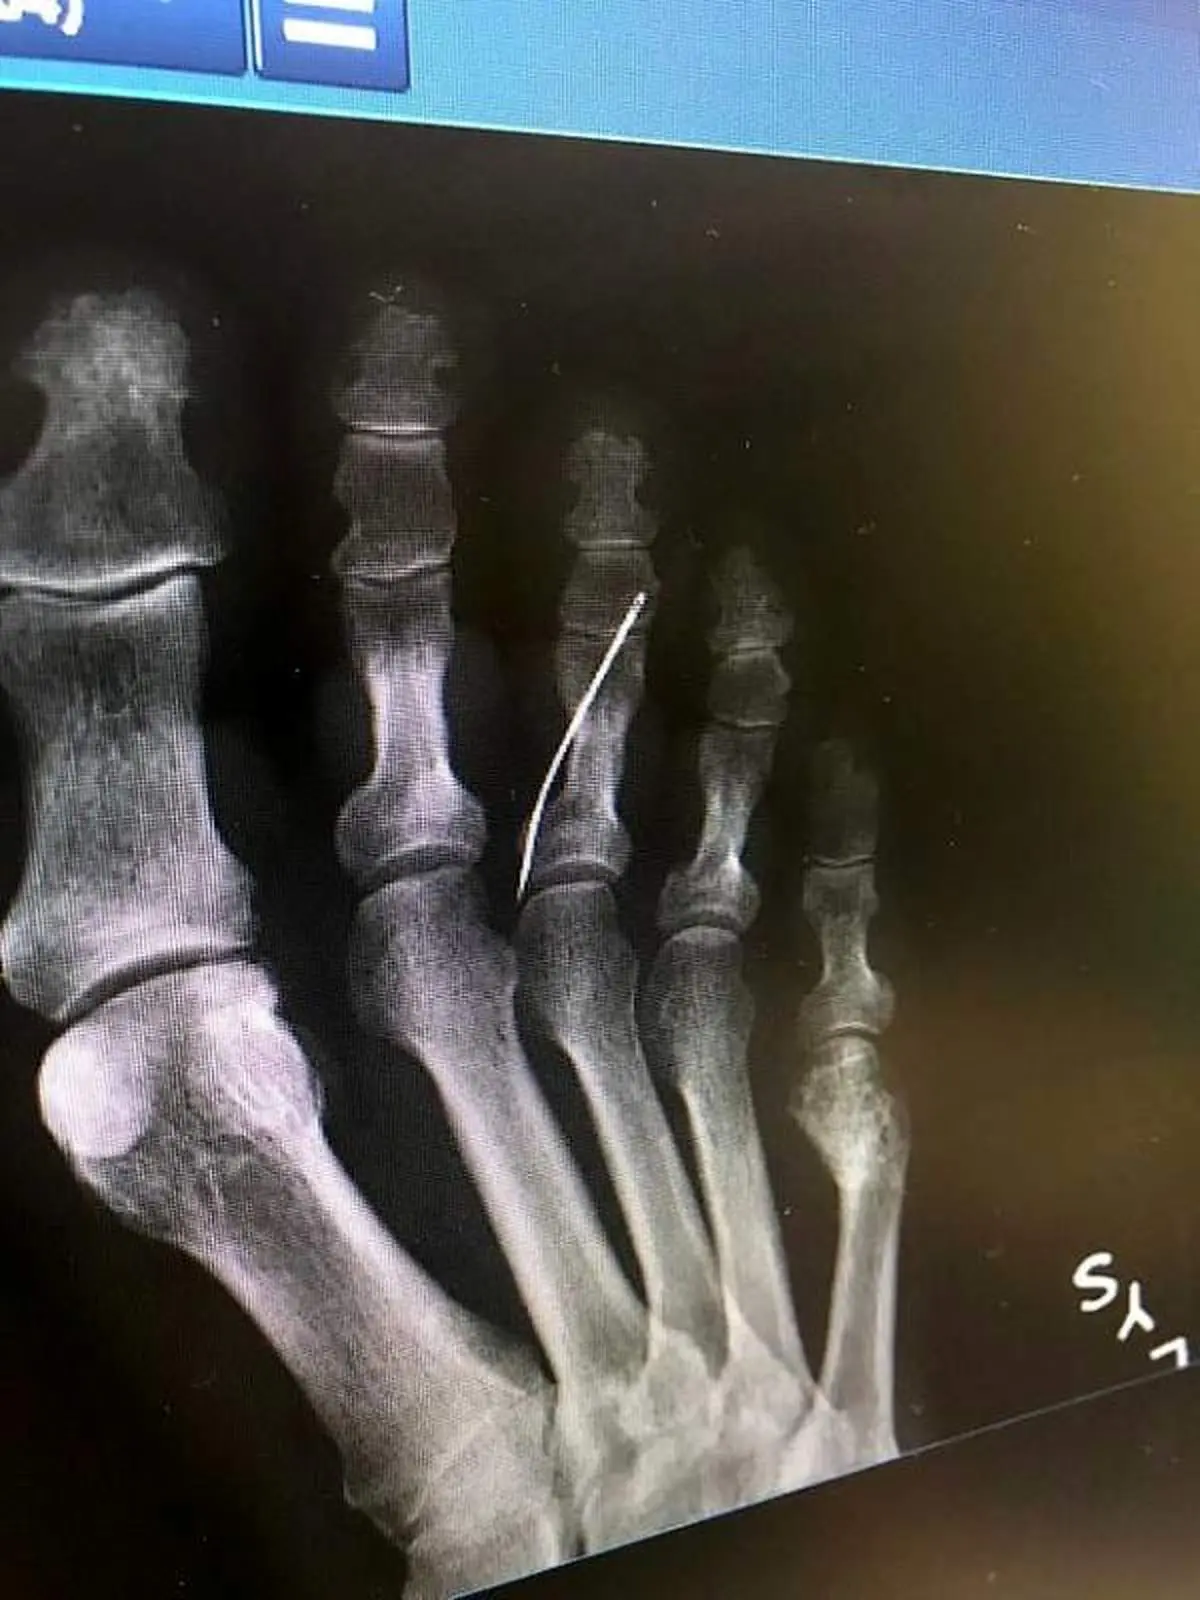

به گزارش منیبان؛ مادربزرگی که نامش منتشر نشده است هنگام عبور از اشعه ایکس متوجه واقعیتی شد که باور کردنی نبود او سوزن خیاطی در پایش داشت که هیچ توجیهی برای آن نداشت .

زنی که نامش ذکر نشده است، به دلیل مرض دیابت حس را در پایش از دست داده است و از وجود سوزنی که در پایش بوده هیچ اطلاعی نداشته. نوه ی او که اهل کالیفرنیا بود تصاویر او را به اشتراک گذاشت کاربران زیادی نظرات متفاوتی داشتند اما او وقتی به پزشک مراجعه کرد سریع او را به طور اورژانسی عمل کرده و سوزن را بیرون آوردن عفونت پای او به حدی بود که باید در بیمارستان می ماند و حالا هیچ معلوم نیست چقدر طول بکشد تا پوستش التیام پیدا کند.